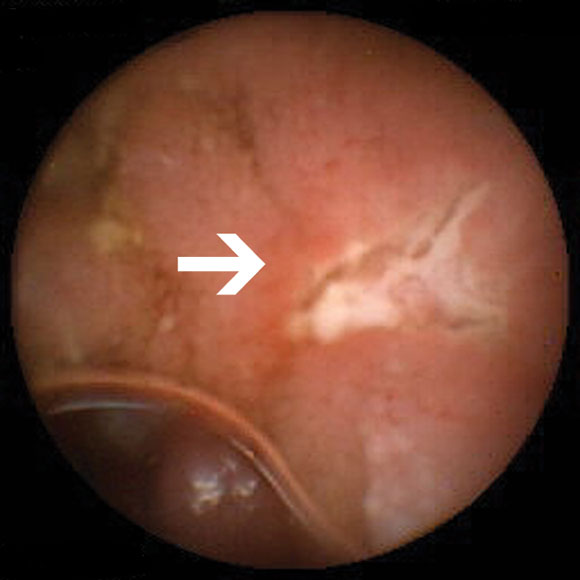

Of the nine patients referred for investigation of small-bowel Crohn's disease, none had been taking non-steroidal anti-inflammatory drugs (NSAIDs) before onset of their symptoms. Small-bowel erosions or ulcers (Box 2B) were seen in seven of these nine patients. Enteroclysis demonstrated mucosal irregularity in two of the seven patients with abnormal findings on capsule endoscopy. Management was changed in five of the nine patients. One patient was lost to follow-up. Changes in management are summarised in Box 4.

In suspected Crohn's disease of the small bowel, our results are similar to other studies. These have reported an increased yield in detecting erosions and ulcers missed by conventional investigations, including ileoscopy and small-bowel barium studies.4,13 Our findings led to a change in management in five out of seven patients followed up (Box 4). We believe that capsule endo-scopy is useful in two distinct situations. First, in investigating patients with suspected de novo small-bowel Crohn's disease based on specific criteria, including abdominal pain, fever, weight loss, anaemia, elevated erythrocyte sedimentation rate but negative results on conventional investigations.4 Second, in patients whose clinical and laboratory findings are out of keeping with the known extent and severity of disease using conventional investigations.